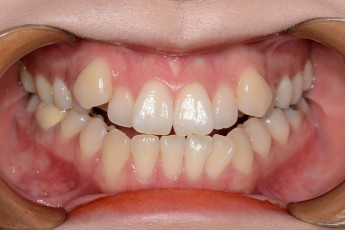

BEFORE & AFTER